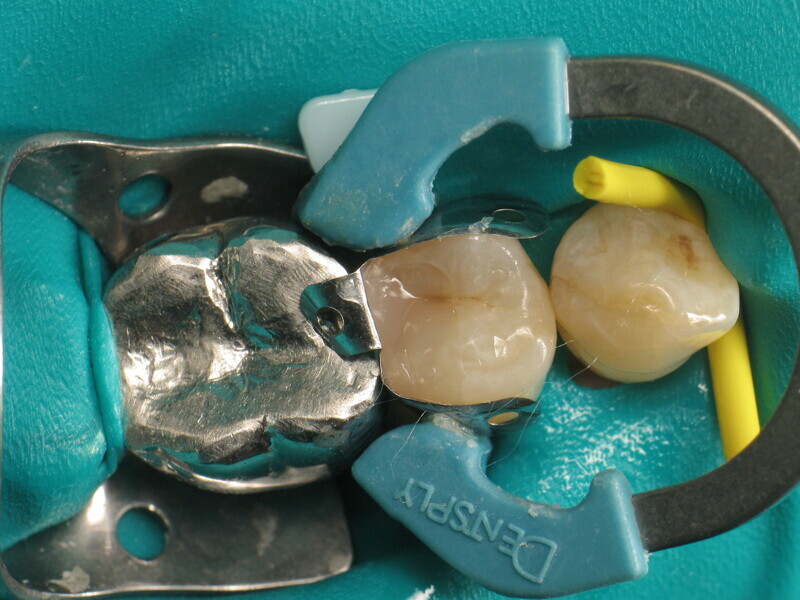

Le cas clinique décrit dans cet article porte sur une cavité de classe II sur une prémolaire (45) qui sera restaurée à l’aide d’un composite thermovisqueux (Fig. 1). La dent est isolée avec une digue en latex (Fig. 2). La cavité de classe II est ensuite nettoyée (Fig. 3). Afin d’obtenir une paroi distale anatomiquement correcte, une matrice, un coin et un anneau sont placés (Fig. 4). L’émail dentaire est ensuite mordancé pendant 30 secondes et la dentine pendant 15 secondes (Conditioner 36, Dentsply Sirona ; Fig. 5) puis rincé abondamment (Fig. 6). En raison de la faible épaisseur de dentine restante, une protection pulpaire (Telio Desensitizer, Ivoclar) est également appliquée (Fig. 7). L’adhésif (Futurabond DC, VOCO) est déposé dans la cavité pendant 20 secondes puis séché 5 secondes sous un jet d’air non gras et enfin, photopolymérisé pendant 10 secondes (Figs. 8 et 9). Pour un mouillage optimal, le fond de la cavité est recouvert d’un composite fluide extrêmement fin (GrandioSO Light Flow, A3.5, VOCO) et durci en 20 secondes (Figs. 10 et 11).